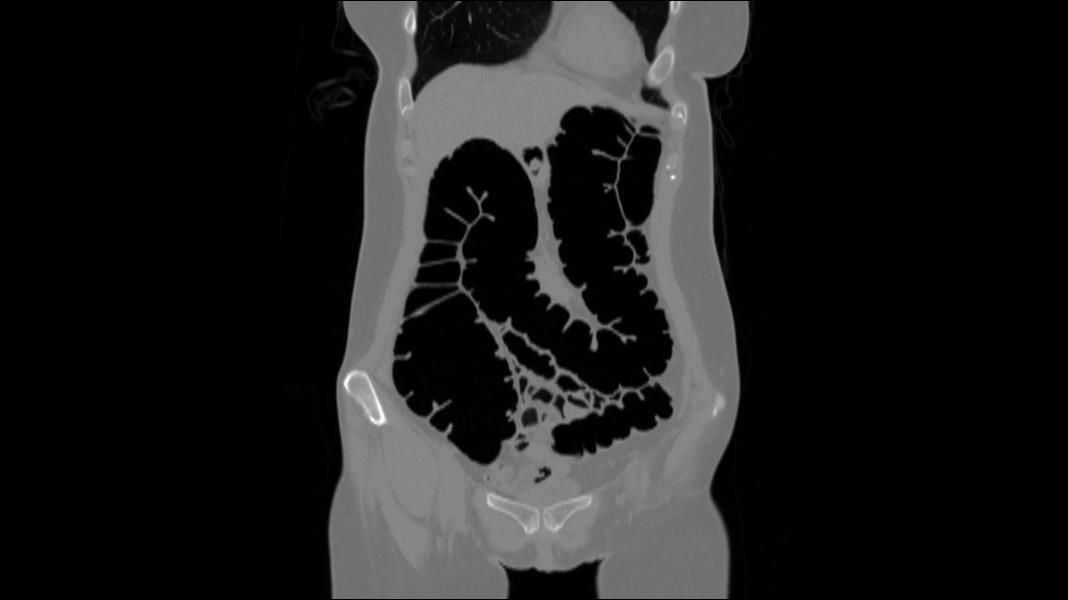

- Virtual colonoscopy uses CT scanning to obtain an interior view of the colon.

Virtual colonoscopies are a more thorough, less invasive form of the traditional colonoscopy because there’s only a 2.5″ insertion. The danger of tearing or perforating the colon walls is removed, and because it’s minimally invasive, there’s no need for anesthesia, eliminating another potential risk.

The images produced from our scans are reviewed by a board-certified radiologist, and a report is created for our patients to share with their physicians.